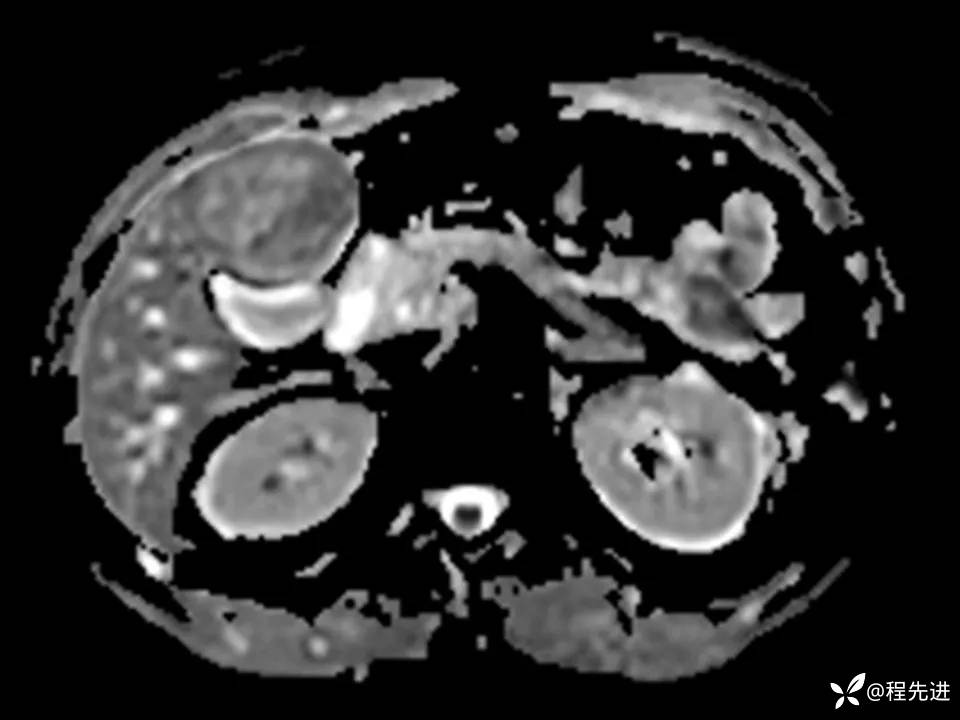

患者性别:男

患者年龄:27岁

简要病史:体检发现肝脏占位2周

既往史:平素体健,无特殊

实验室检查:(-)